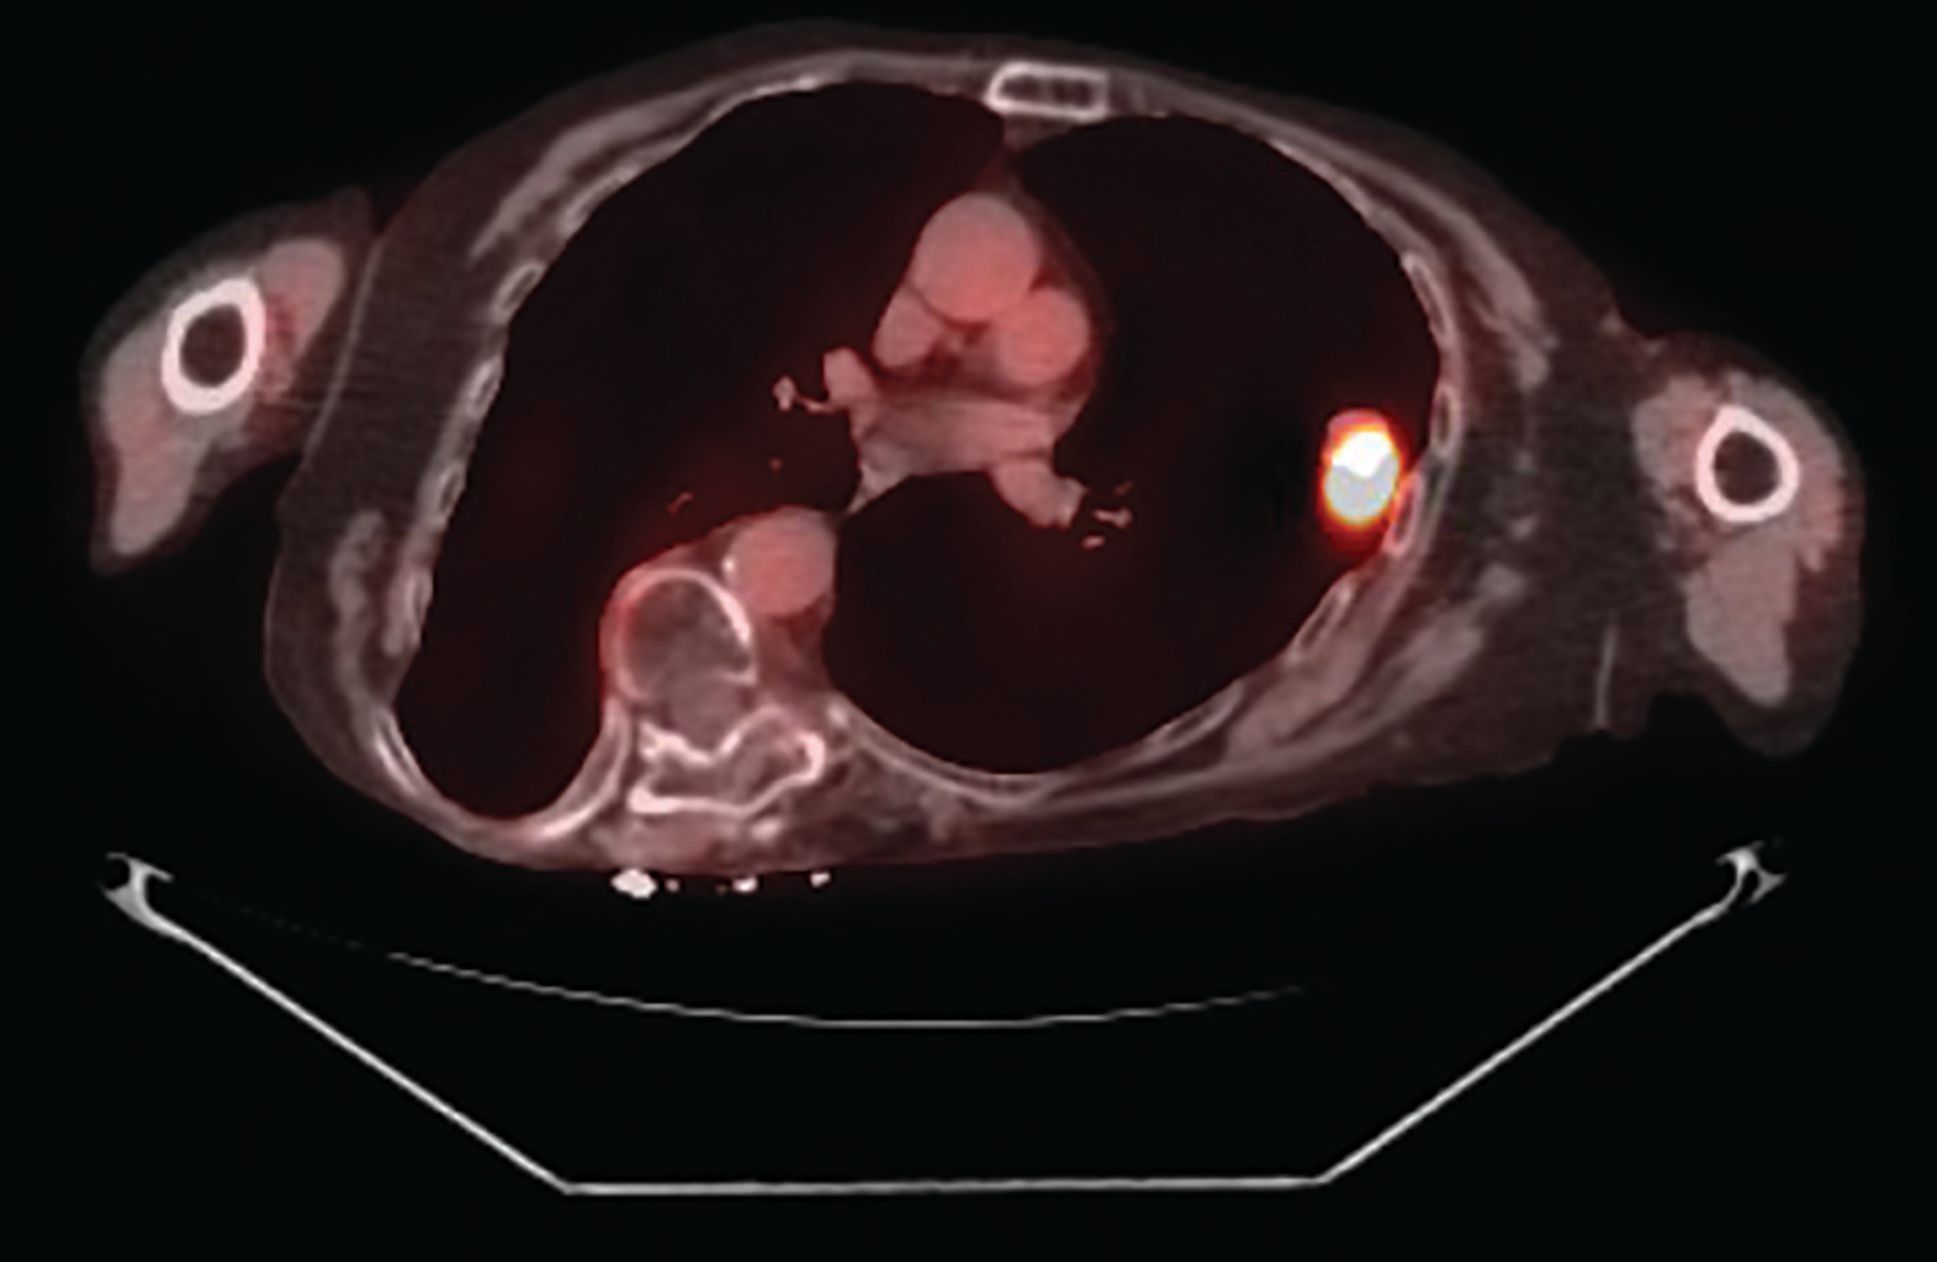

Figure 2A: 2.5 cm left upper lobe lesion with an SUV of 12.7.

Figure 2B: 1.1 cm right upper lobe lesion with SUV of 2.1.

A 70-year-old white woman with a 40 pack-year history of smoking has been on follow-up for previously detected abnormal lung nodules during the past 3 years. The most recent computed tomography (CT) scan revealed an increase in the size of the left upper lobe nodule-from 4 mm a year ago to 2 cm on the current CT scan. A CT-guided needle biopsy of this nodule revealed small cell lung carcinoma (Figures 1A and 1B). Further work-up with a positron emission tomography (PET) scan confirmed the left upper lobe lesion with a standard uptake value (SUV) of 12.7, and also revealed a right upper lobe nodule (1.1 cm in size) with an SUV of 2.1 (Figures 2A and 2B). Following multidisciplinary evaluation at the thoracic oncology tumor conference, the patient underwent initial bronchoscopy with ultrasound (endobronchial ultrasound [EBUS]) and biopsy of lymph node levels 10, 7, and 4, followed by a right-sided video-assisted thoracoscopic surgery (VATS) and a wedge resection of the right upper lobe nodule, and a left upper lobe lobectomy (Figure 3). Mediastinal lymph node dissection revealed no lymph node involvement. Pathology of the right upper lobe wedge resection revealed a 1.3-cm non–small cell lung adenocarcinoma, and pathology of the left upper lobe lobectomy revealed a 2.5-cm small cell lung carcinoma (Figures 4A and 4B). Both tumors had visceral pleural involvement and were resected with clear margins. The right upper lobe tumor was staged as pT2N0 and the left upper lobe tumor was staged as pT2N0 (per the 8th edition of the American Joint Committee on Cancer staging system).